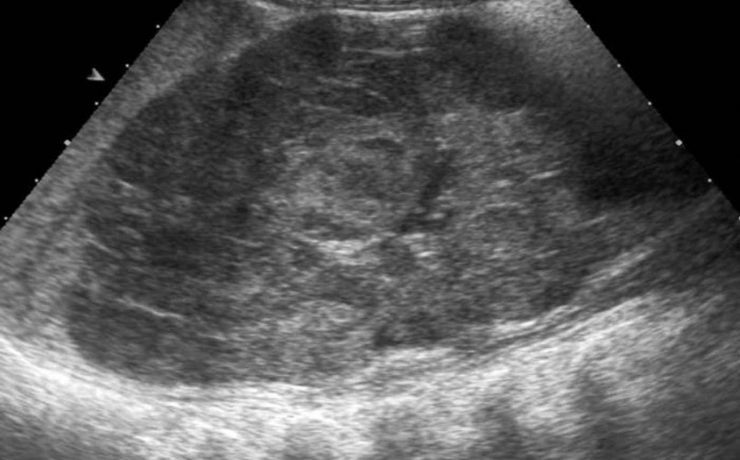

El ultrasonido (US) musculo esquelético

El ultrasonido (US) musculo esquelético es una técnica de exploración cada vez más utilizada , ya que permite de manera inocua, cómoda, dinámica, a bajo costo y con una gran sensibilidad explorar en tiempo real un área anatómica como el hombro. La técnica ha sido progresivamente adoptada por los clínicos